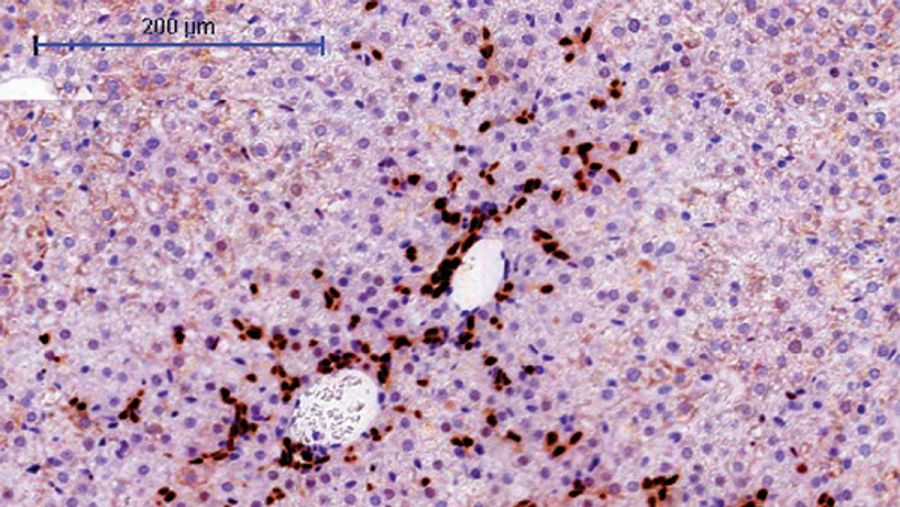

Sección del hígado de un modelo de ratón en el que los hepatocitos expresan el oncogen URI. CNIO

Sección del hígado de un modelo de ratón en el que los hepatocitos expresan el oncogen URI. CNIO CNIO